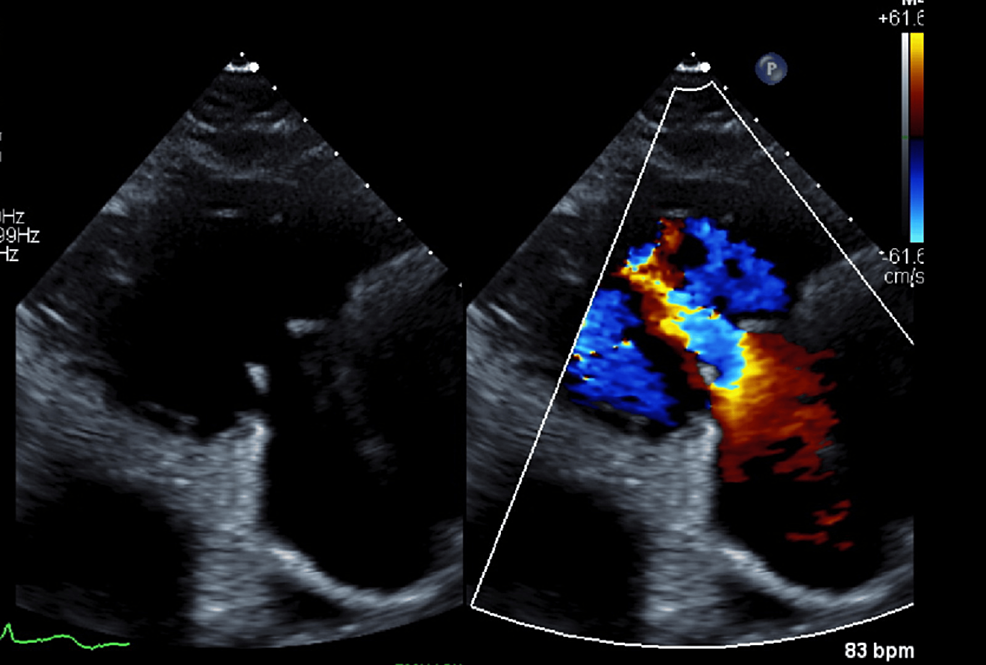

From www.researchgate.net

Transthoracic echocardiographic images demonstrating enlarged What Is Borderline Enlarged Heart Your heart may be unusually thick or. Your heart can become enlarged when it. An enlarged heart, also known as cardiomegaly, can lead to serious health problems such as heart failure, stroke, or even sudden death. An enlarged heart (cardiomegaly) describes a heart that’s bigger than what is typical. Your heart can become enlarged if the muscle works so hard. What Is Borderline Enlarged Heart.